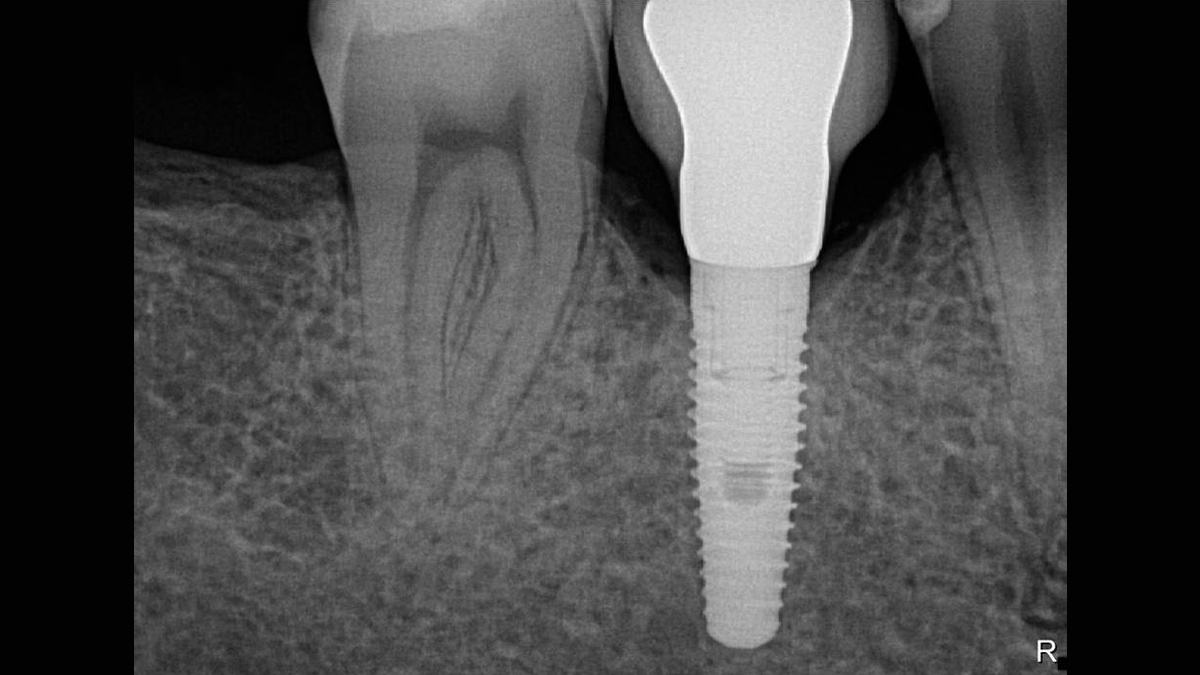

Excellent Image Quality

Xios XG Supreme provides a theoretical resolution of 33 lp/mm and a 15 μm pixel size.

Working with Xios XG Supreme: Filtering enhancements

With Xios XG Supreme sensors you have the option of five different filtering options: General Dentistry, Endodontics, Periodontics, Restorative and Hygiene. These clinically specific views are designed to optimize your diagnosis, enhancing the image to suit your needs.

Gallery of Sample Images